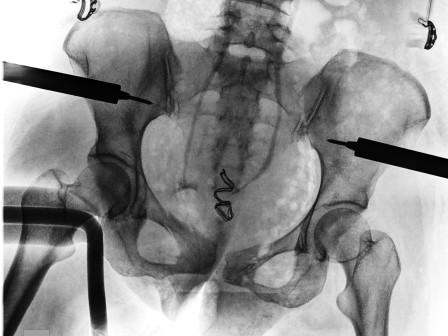

Choc hémorragique